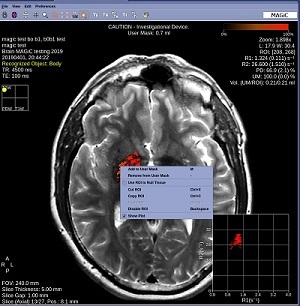

Figure 3. ROI right-click menu

3. Click Add to User Mask.

• All voxels within the ROI are added to the user mask. The total volume of each voxel is included in the user mask volume.

4. Click Remove from User Mask.

• All voxels within the user mask ROI are removed.

5. Click Use ROI to Null Tissue.

• The contrast /color of the user mask remains the same, but all pixels within the image that are the have the same pixel intensity are turned black. For example, if your user mask ROI is inside pathology, Use ROI to Null Tissue to change all other pixels with the similar intensity as the pathology to black. This is done through an inversion pre-pulse with an optimized TI.

6. Click Cut ROI, Copy ROI, Paste ROI, Disable ROI to modify the ROI.

7. Click Show Plot to toggle the plot in the lower right corner on/off.